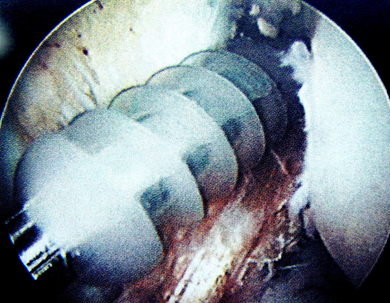

關(guān)節(jié)鏡下見重建的前交叉韌帶